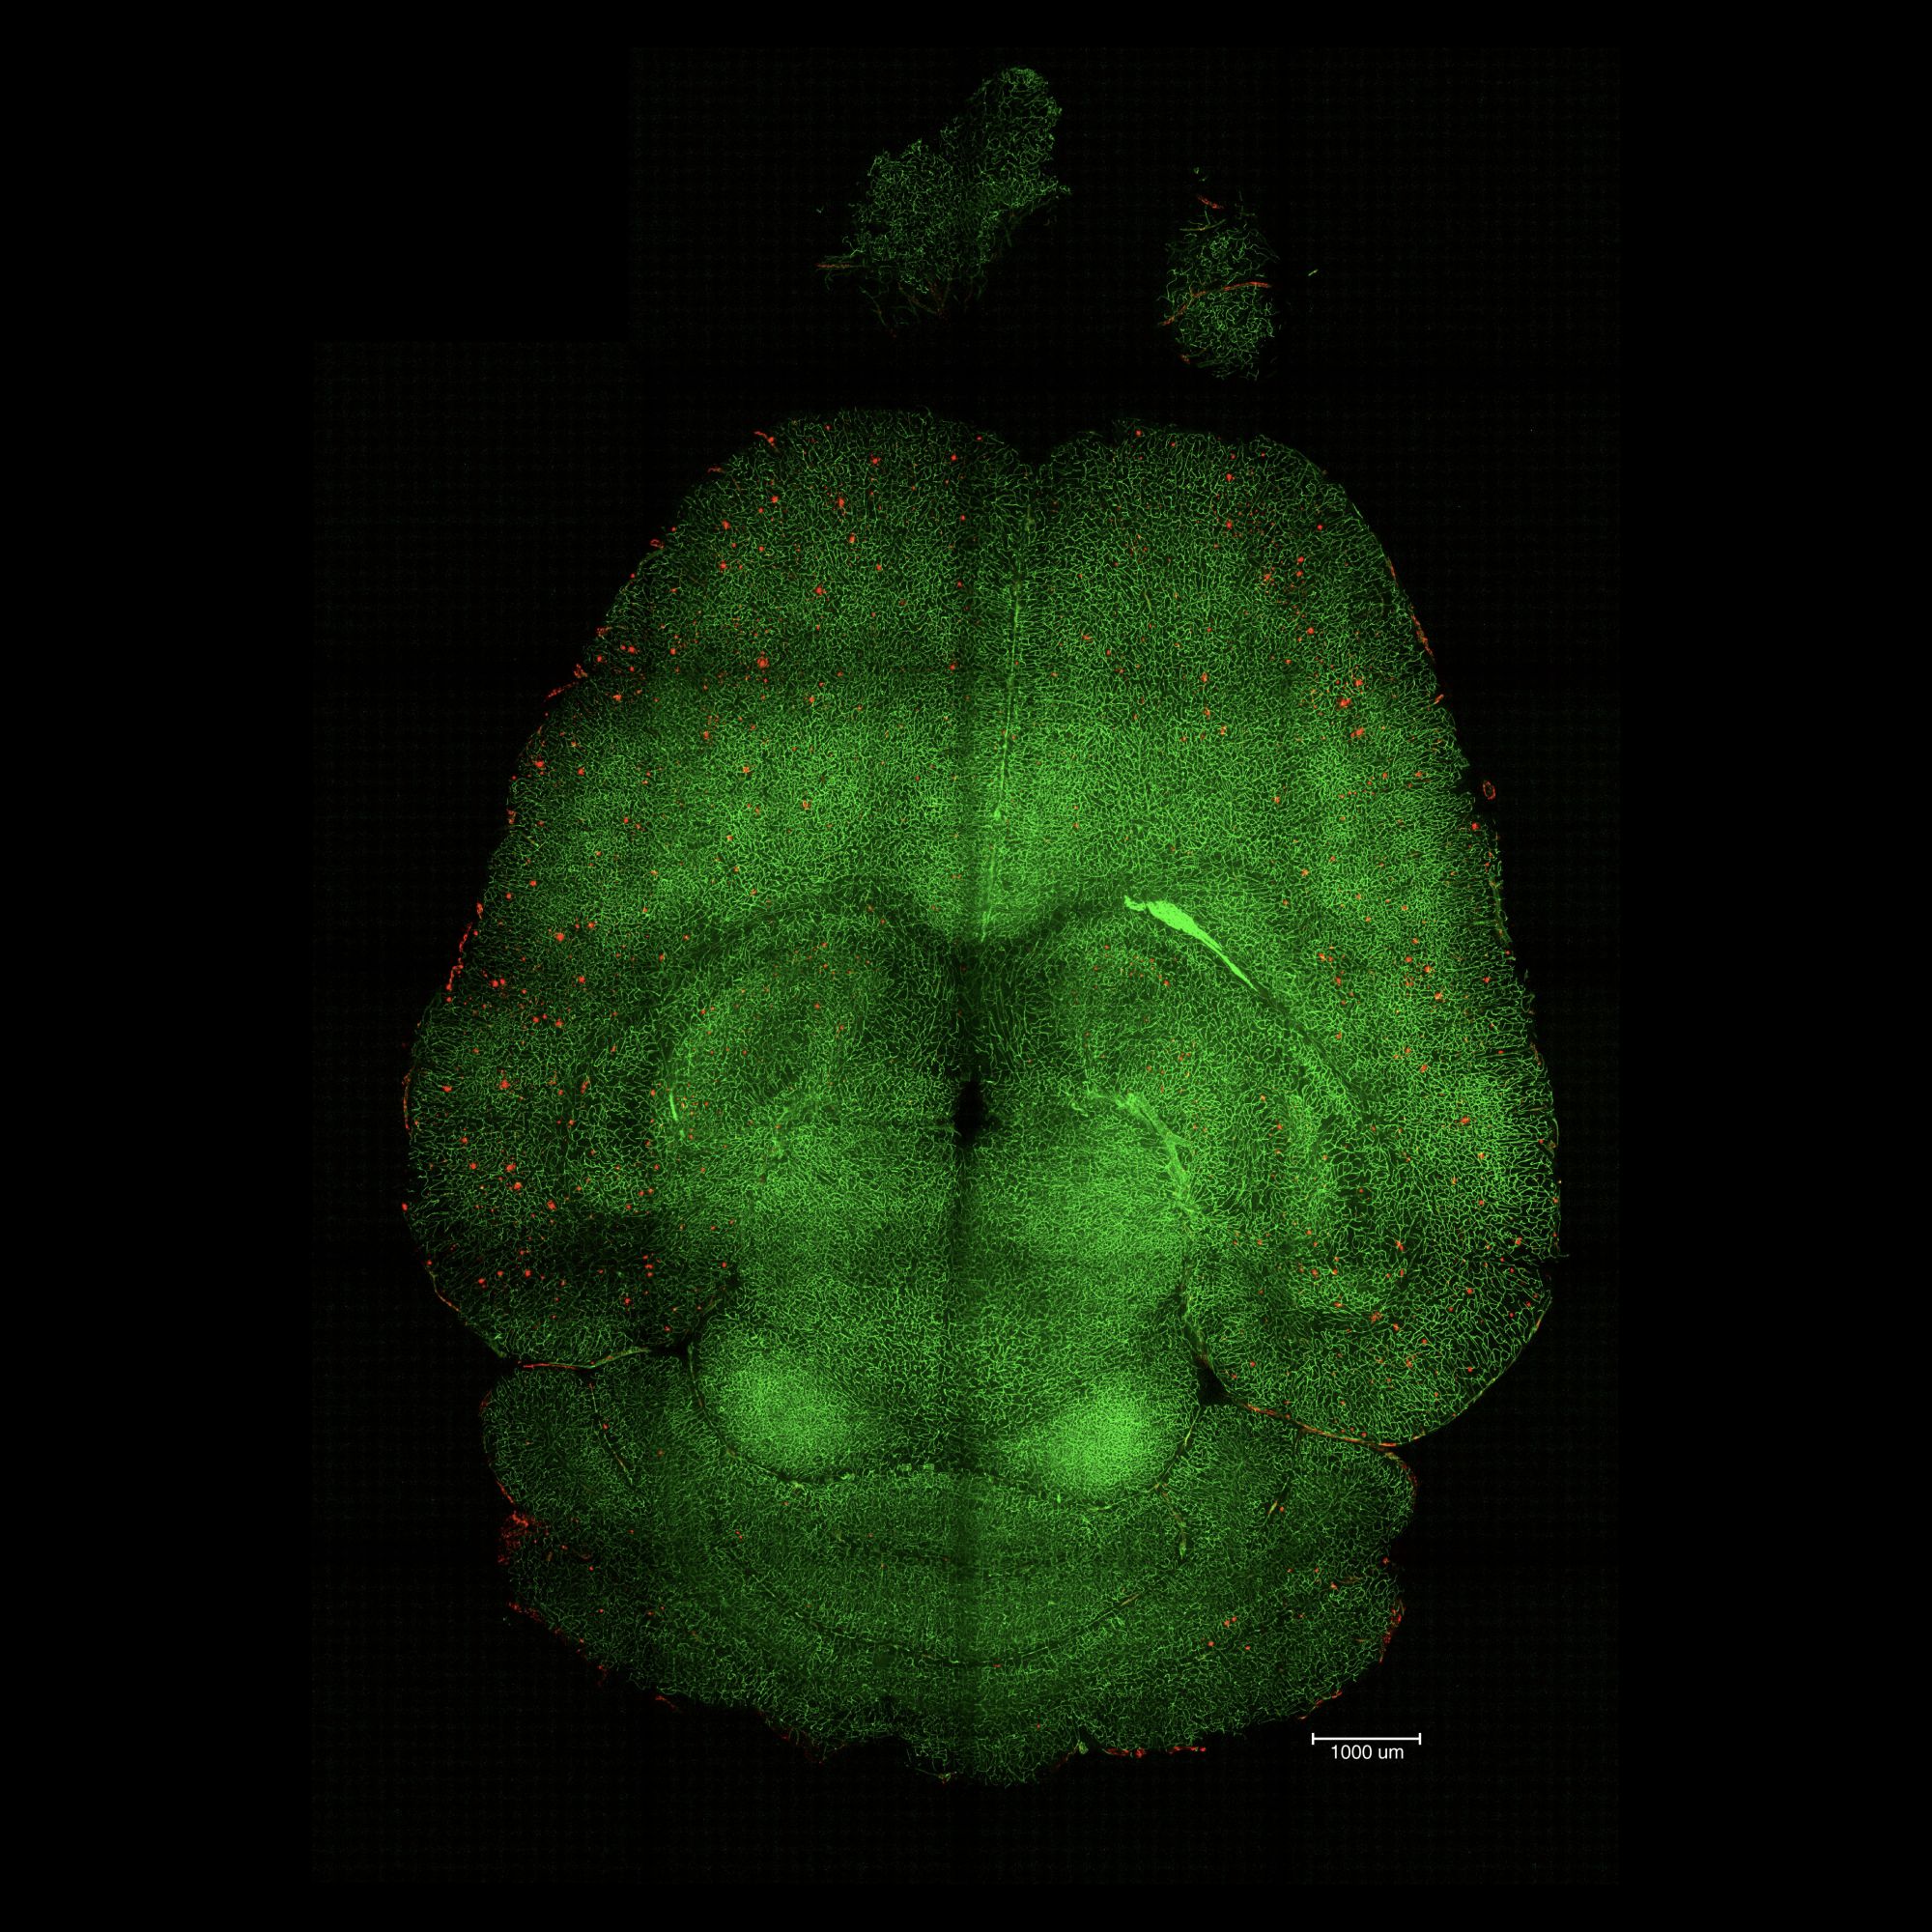

Zaledwie trzy zastrzyki z nanocząstek wystarczyły, by u myszy z chorobą Alzheimera doszło do zaskakującej pozytywnej poprawy. Naukowcy z Uniwersytetu w Syczuanie, Katalońskiego Instytutu Bioinżynierii (IBEC) i University College London zastosowali podejście polegające na wzięciu na cel naczyń krwionośnych, a nie neuronów czy innych komórek mózgu. Ze szczegółami ich badań można zapoznać się na łamach Signal Transduction and Targeted Therapy.

Zastosowane leczenie przywróciło normalne funkcjonowanie bariery krew-mózg, co skutkowało odwróceniem skutków alzheimera w mysim modelu choroby. Bariera ta chroni mózg przed kontaktem ze szkodliwymi substancjami i mikroorganizmami. W przebiegu choroby Alzheimera taką główną szkodliwą substancją są białka beta-amyloidu (Aβ), tworzące blaszki amyloidowe, uniemożliwiające prawidłowe funkcjonowanie neuronom.

Junyang Chen, badacz ze Szpitala Wschodniochińskiego na Uniwersytecie w Syczuanie, a obecnie doktorant na University College London poinformował, że już po 1. wstrzyknięciu nanocząstek zaobserwowano spadek ilości Aβ w mózgu o 50–60 procent. Jednak najbardziej uderzający był wpływ leczenia na myszy. Zwierzęta były genetycznie zmodyfikowane tak, by rozwinęła się u nich choroba Alzheimera. Podczas jednego z eksperymentów 12-miesięczna mysz (odpowiednik 60-letniego człowieka) otrzymała nanocząstki, a po 6 miesiącach zbadano, jak się zachowuje. Okazało się, że 18-miesięczne zwierzę (odpowiedni 90-letniego człowieka) funkcjonowała tak, jak jej zdrowe rówieśniczki.

Długoterminowy wpływ naszej terapii bierze się z odtworzenia sieci naczyń krwionośnych mózgu. Uważamy, że działa to kaskadowo: gdy w mózgu akumuluje się toksyczny Aβ, choroba postępuje. Gdy jednak sieć naczyń krwionośnych zostanie przywrócona do prawidłowego stanu, dochodzi do wyczyszczenia mózgu z Aβ i innych szkodliwych substancji, dzięki czemu cały układ odzyskuje równowagę, mówi profesor Giuseppe Battaglia z IBEC.

Jednym z głównych problemów w chorobie Alzheimera jest zaburzenie prawidłowego funkcjonowania mechanizmów oczyszczających mózg ze szkodliwych substancji. Rolę strażnika utrzymującego odpowiedni poziom Aβ w mózgu pełni proteina LRP1. Rozpoznaje ona beta-amyloid, łączy się z nim i przemieszcza przez barierę krew-mózg do krwioobiegu, gdzie całość zostaje usunięta. Jednak gdy LRP1 połączy się z Aβ zbyt ściśle lub zbyt luźno, transport zostaje zaburzony i beta-amyloid nie jest usuwany.

Przygotowane przez naukowców nanocząstki same działają jak leki, a nie jak nośniki substancji leczniczych. Mają precyzyjnie kontrolowane rozmiary i wyposażone są w określoną liczbę ligand, przez co w specyficzny sposób wchodzą w interakcje z receptorami komórkowymi. Pozwala to na przywrócenie prawidłowego funkcjonowania układu krwionośnego oraz oczyszczenie mózgu z Aβ.